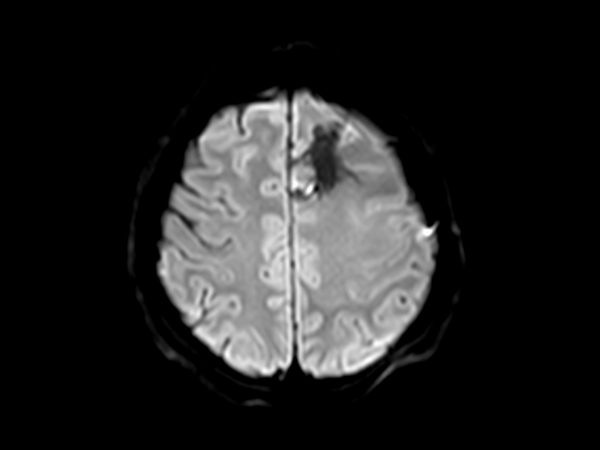

SmartSpeed Precise imaging for brain with glioblastoma

Kyushu University Hospital Japan